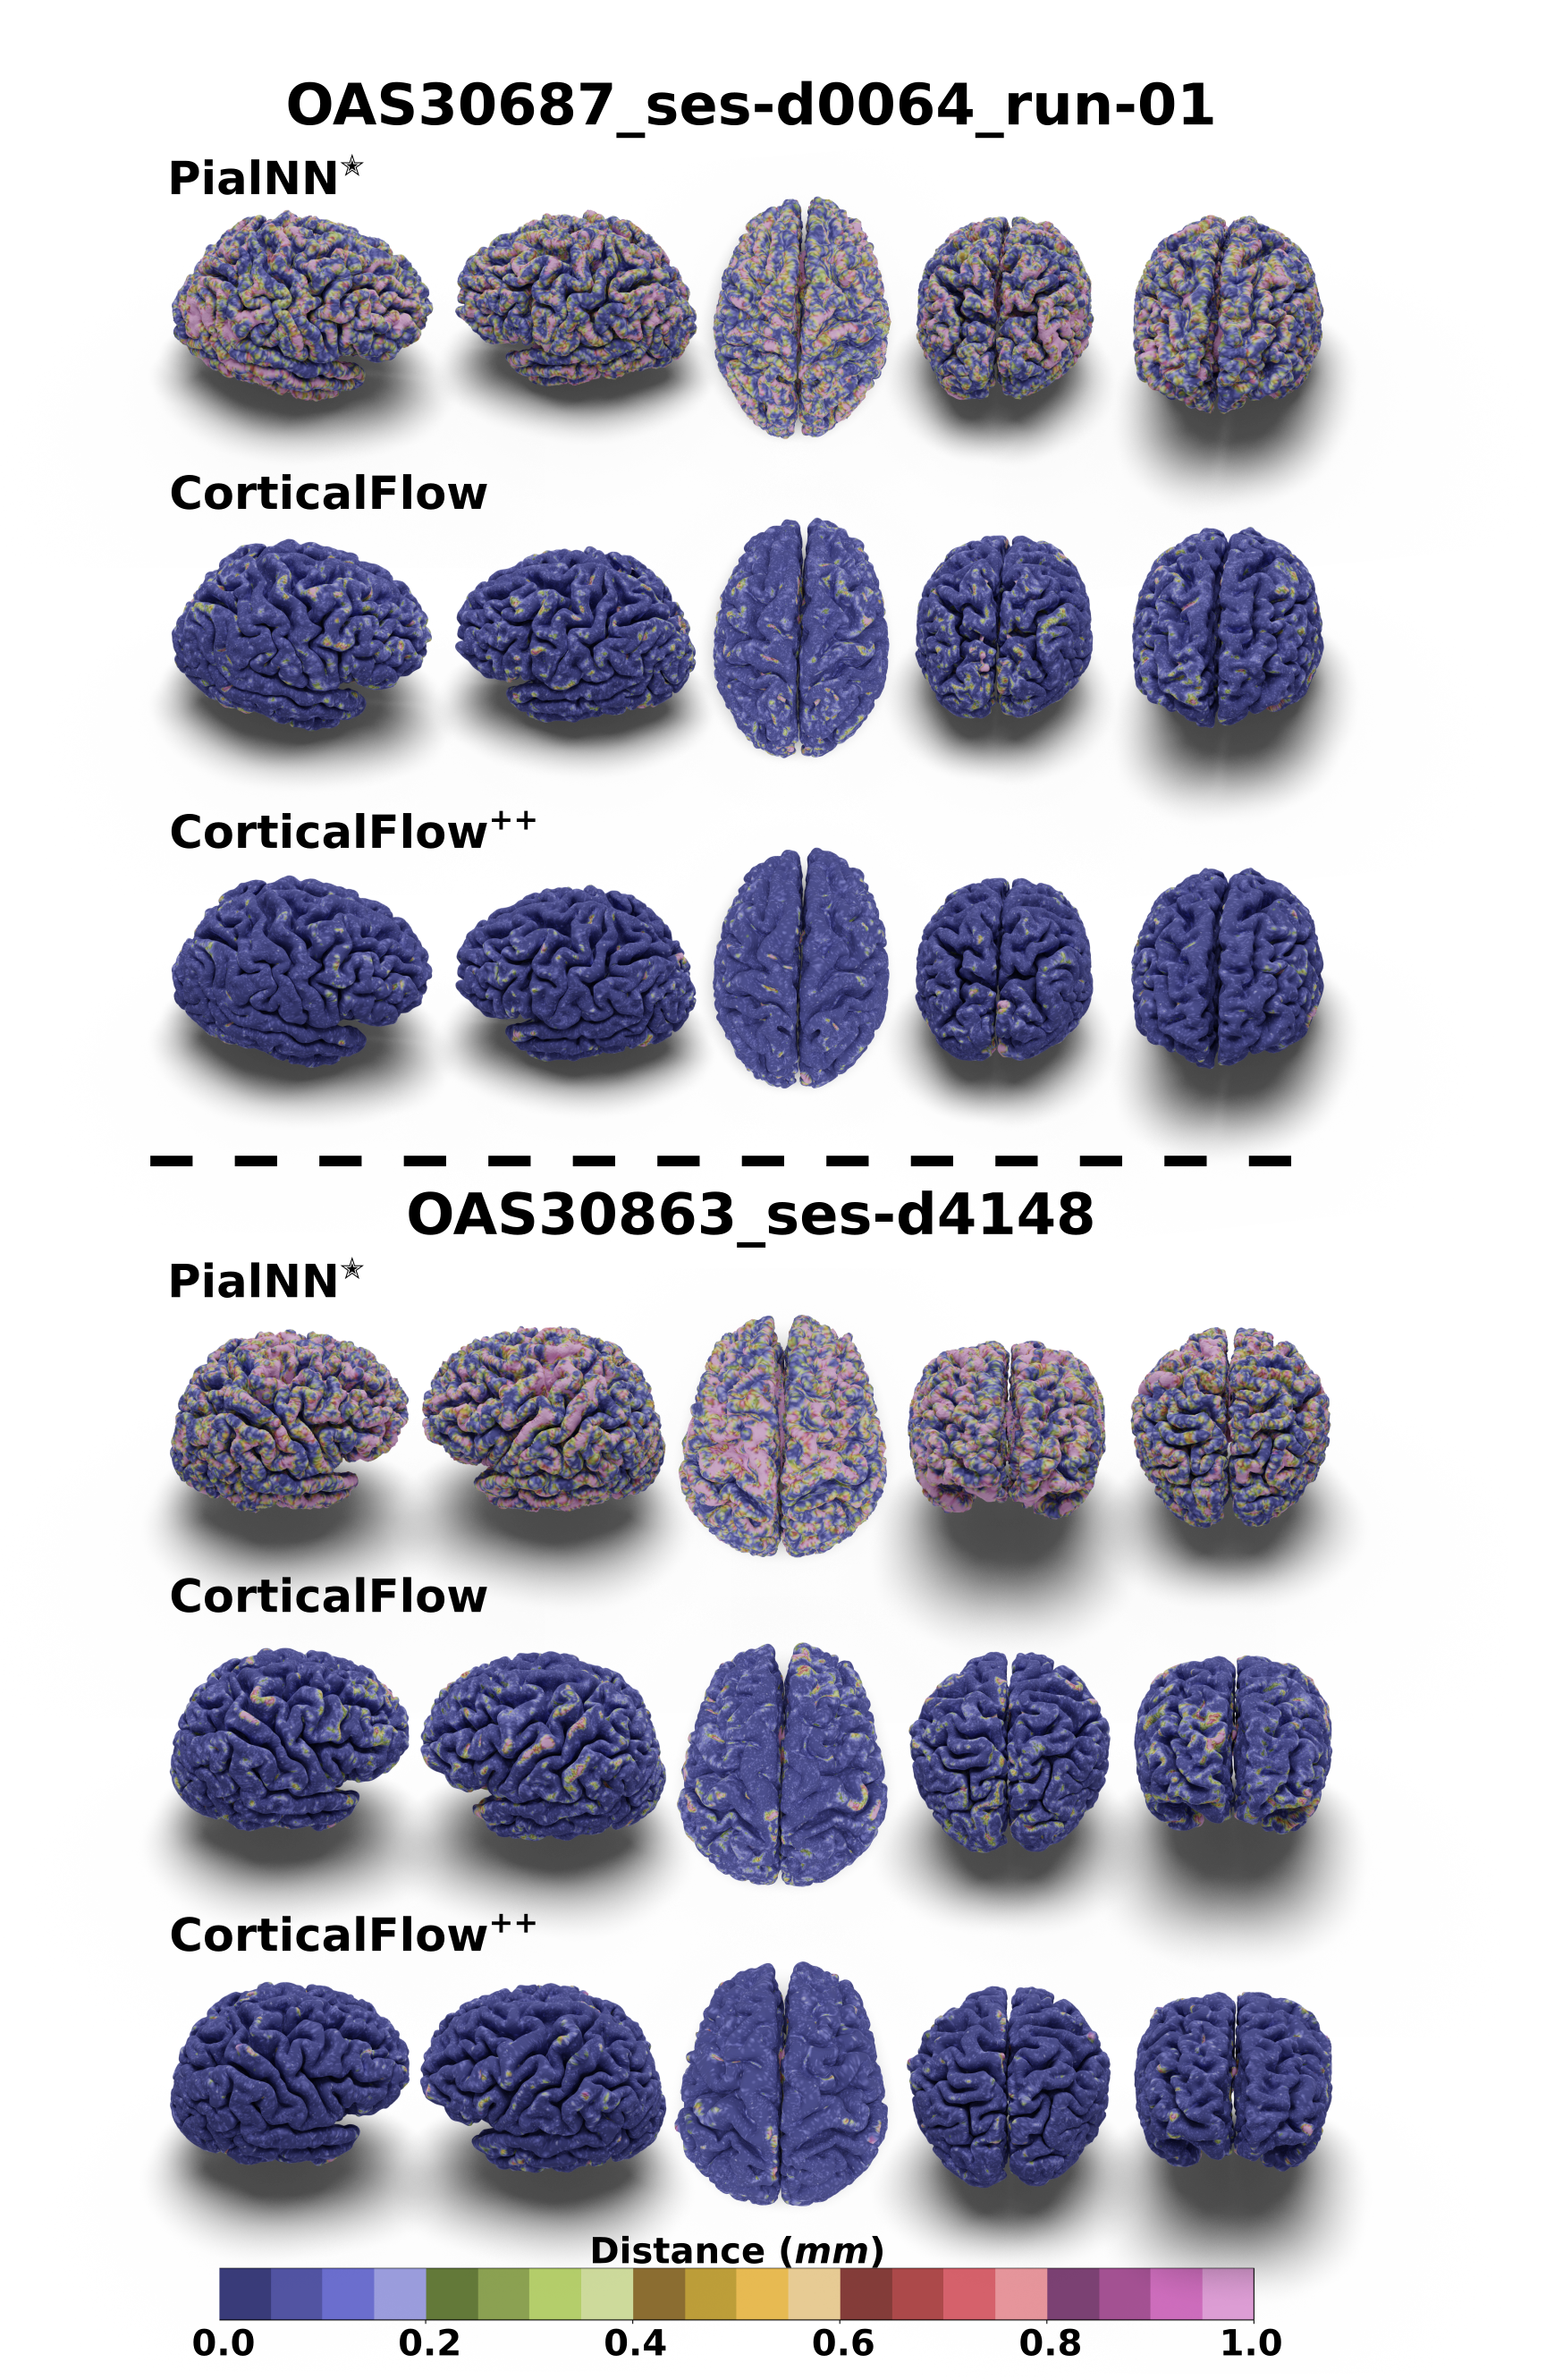

Refer to caption

Figure 2: Predicted cortical surfaces color-coded with the distance to the pseudo-ground-truth surfaces. See our supplementary materials for more examples.

We observe that the adoption of the RK4𝑅𝐾4RK4 ODE solver (CorticalFlow + RK4) and the white to pial surface morphing formulation (CorticalFlow + W2P) significantly improves the geometric accuracy and surface regularity of the CorticalFlow baseline. For instance, we noticed an average decrease of 12.2% and 21.02% in chamfer distance, respectively. Likewise, the percentage of self-intersecting faces reduces on average by 35.90% and 79.19%, respectively. On the other hand, the proposed new templates (CorticalFlow + NEWTPL) present a modest improvement in those criteria, but greatly succeeds in suppressing mesh artifacts as qualitatively shown in Figure 2. Additionally, none of these changes incur a significant increase in reconstruction time or memory consumption due to their GPU friendly nature. All together, these modifications in CorticalFlow++ establish a new state-of-the-art method for cortical surface reconstruction.

Figure 3: Predicted cortical surfaces for subject 099_S_0551_m36 in ADNI dataset. The surfaces are color-coded with the distance to the pseudo-ground-truth surfaces.